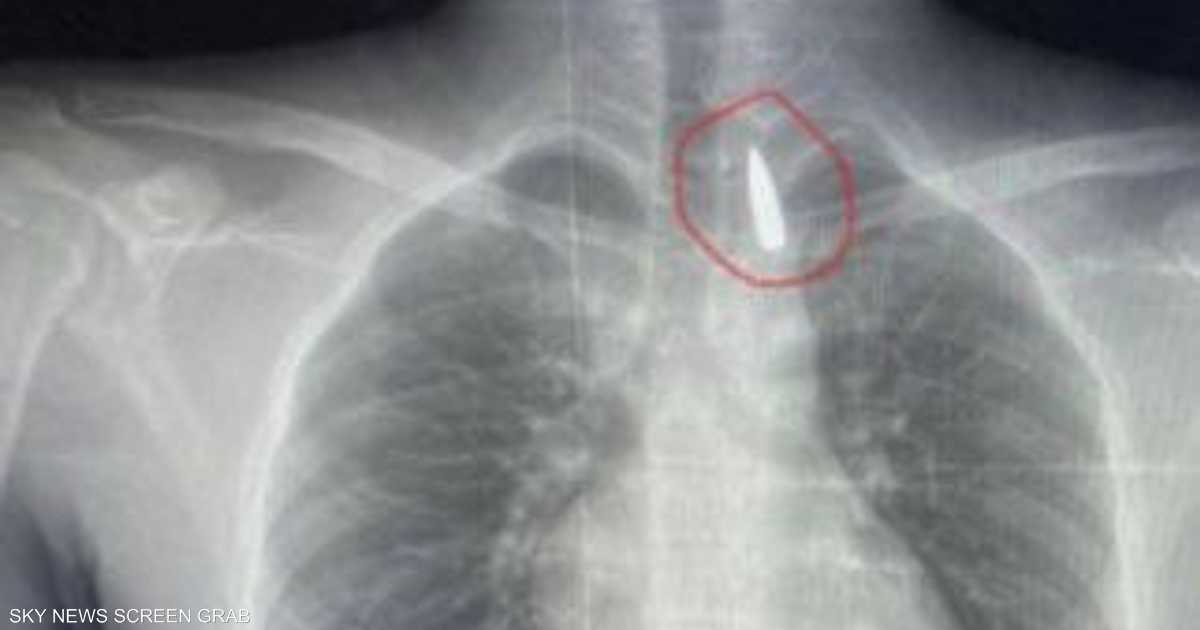

وأوضح عميد كلية الطب جامعة الإسكندرية ورئيس مجلس إدارة المستشفيات الجامعية تامر عبد الله، أن فريق من أطباء قسم جراحة القلب والصدر والتخدير والمعاونين تكمنوا من إجراء جراحة دقيقة بالغة الخطورة لأحد المرضى من قطاع غزة، والذي كان قد تعرض لإصابة بطلق ناري منذ فترة، استقر المقذوف على إثرها داخل تجويف القفص الصدري قرب الشريان الأورطي.

وأضاف في بيان نشرته جامعة الإسكندرية عبر صفحتها على “فيسبوك” أن الشريان الأورطي هو أكبر وأهم شرايين الجسم والمسؤول عن تغذية جميع الأعضاء الحيوية.

مبينا أن الفريق الطبي نجح، رغم دقة الحالة وتعقيدها، في استخراج المقذوف بأمان بعد عملية جراحية استمرت عدة ساعات داخل المستشفى الجامعي الجديد، حيث خضع المريض بعدها للرعاية الطبية اللازمة، مؤكدا أن حالة المريض حاليا مستقرة وتحت المتابعة الدقيقة من الفريق المختص.

وأكد أن استخراج مقذوف مستقر بالقرب من الشريان الأورطي يتطلب دقة متناهية، وتنسيقا تاما بين تخصصات الجراحة العامة و جراحة الأوعية الدموية، والتخدير، والأشعة، والرعاية المركزة.